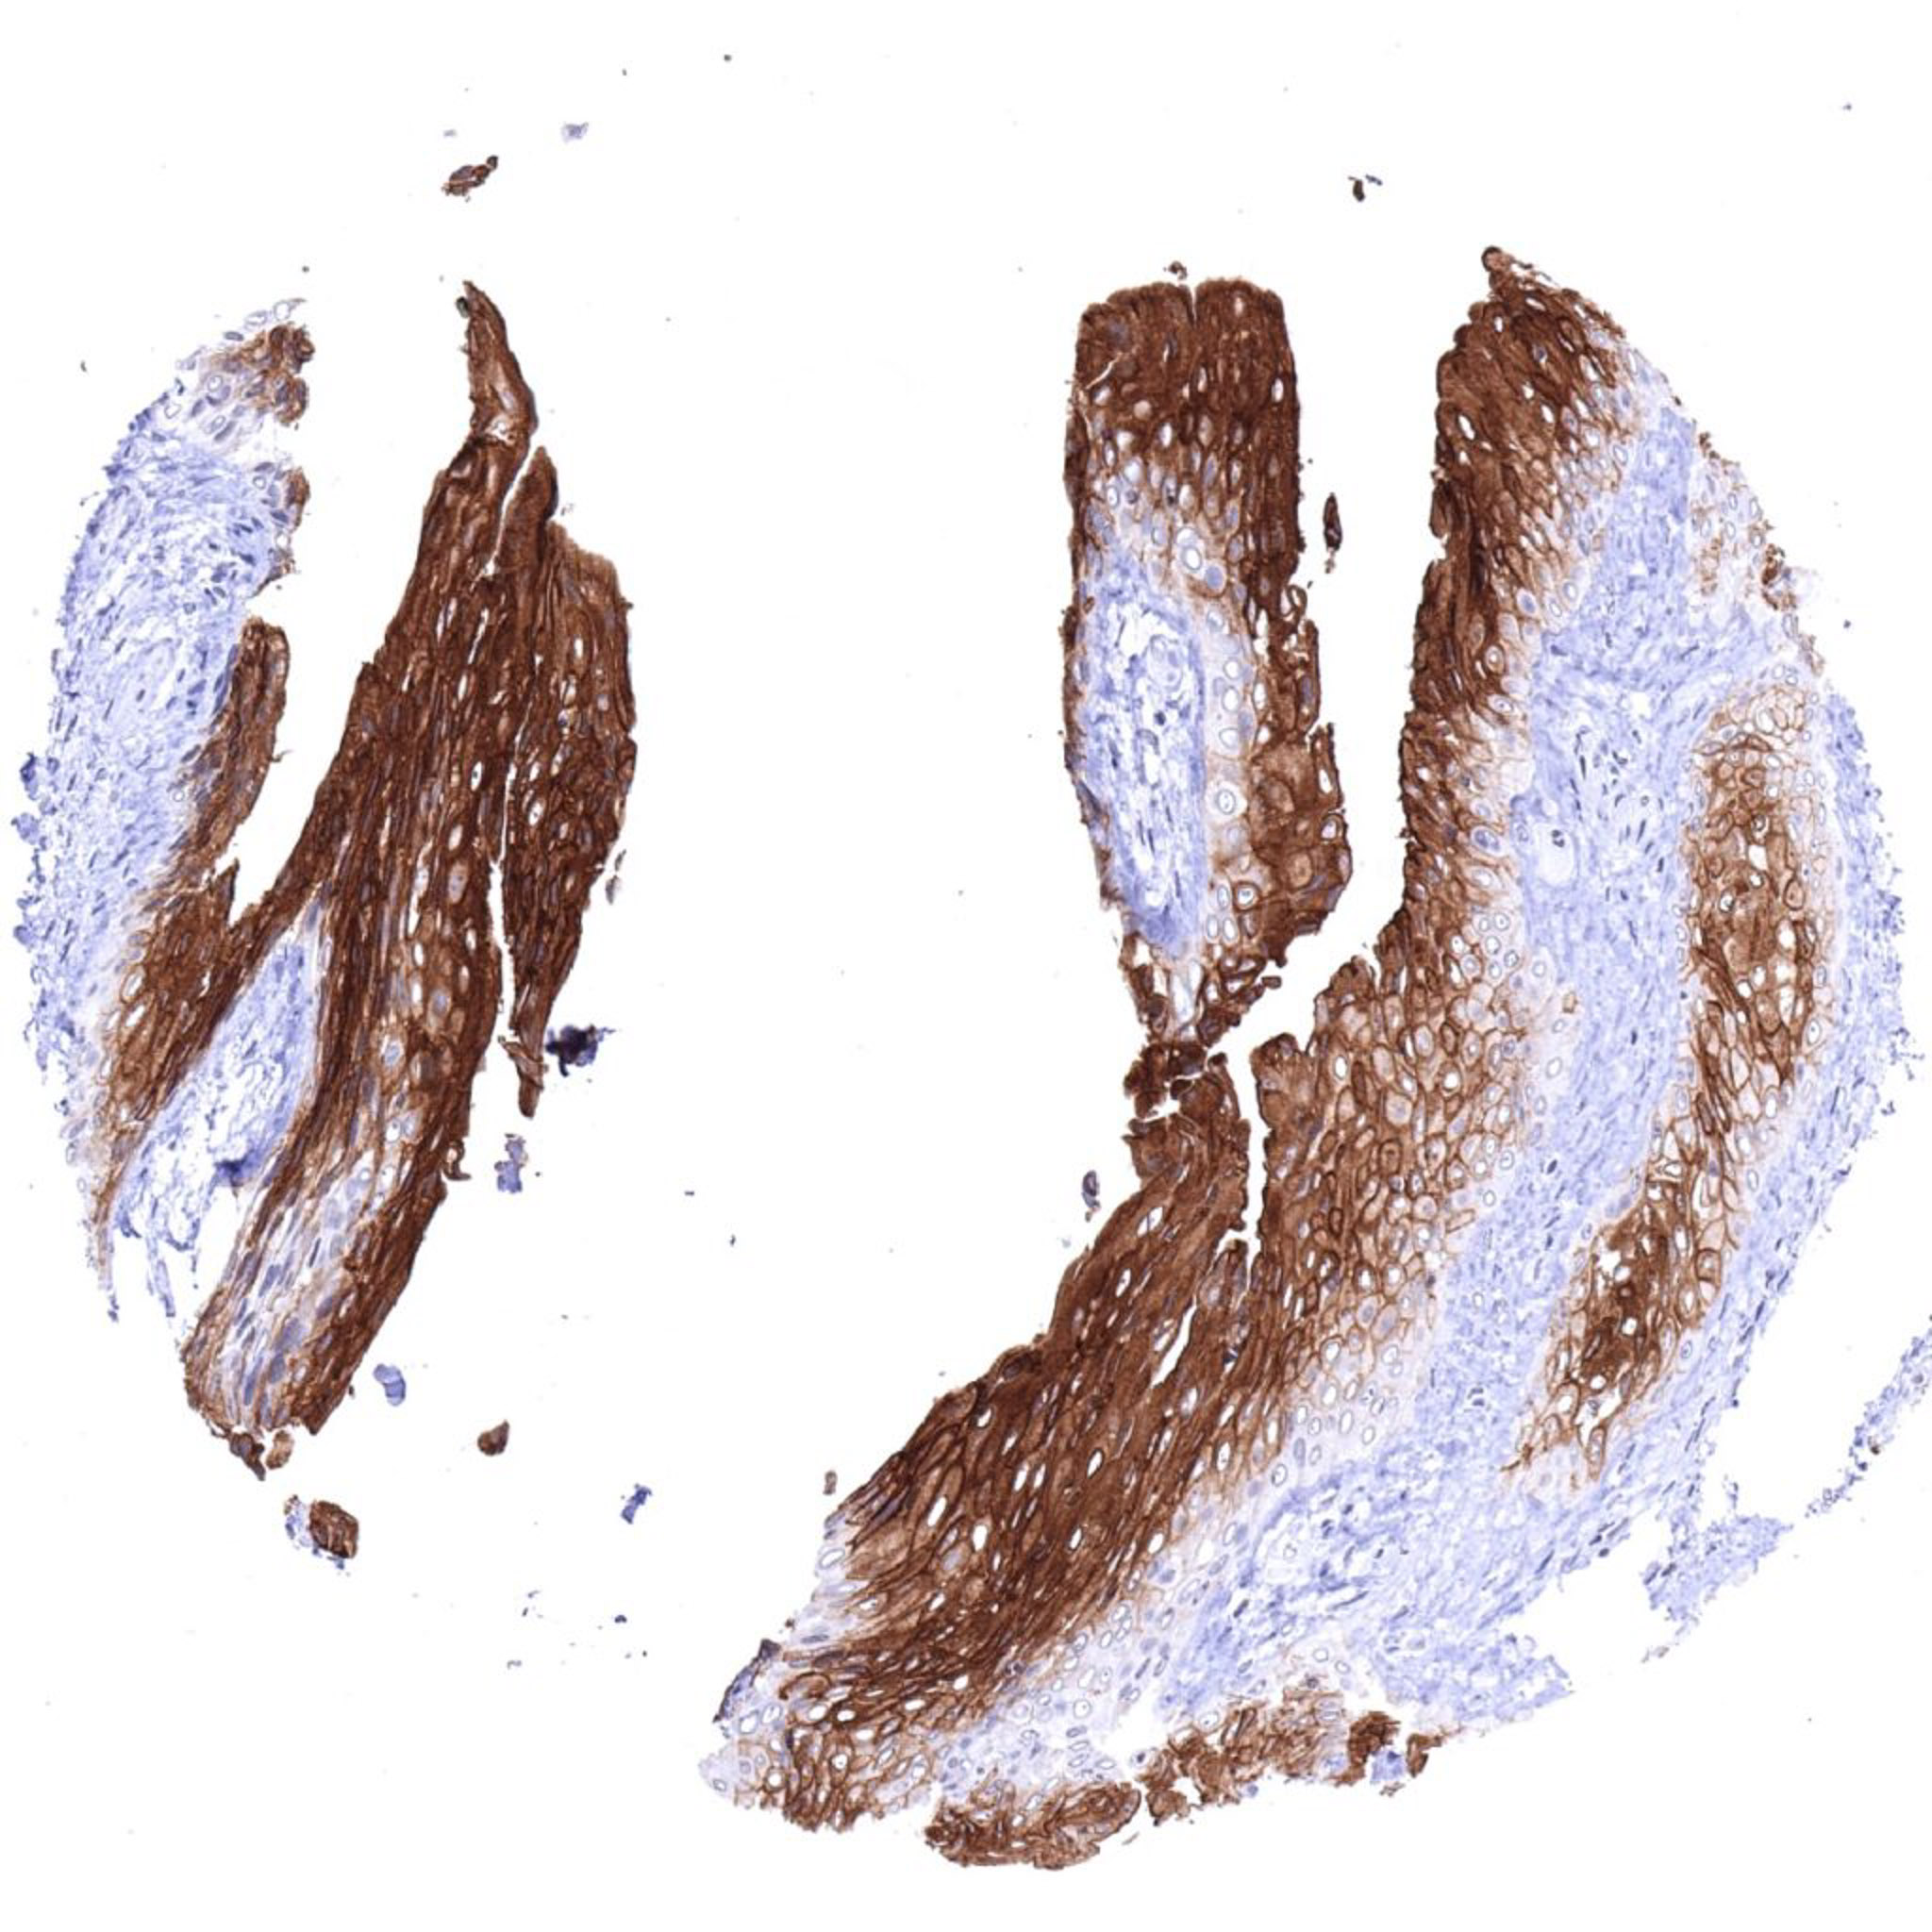

Urinary bladder, urothelium – Strong UPK1B staining in suprabasal urothelial cells